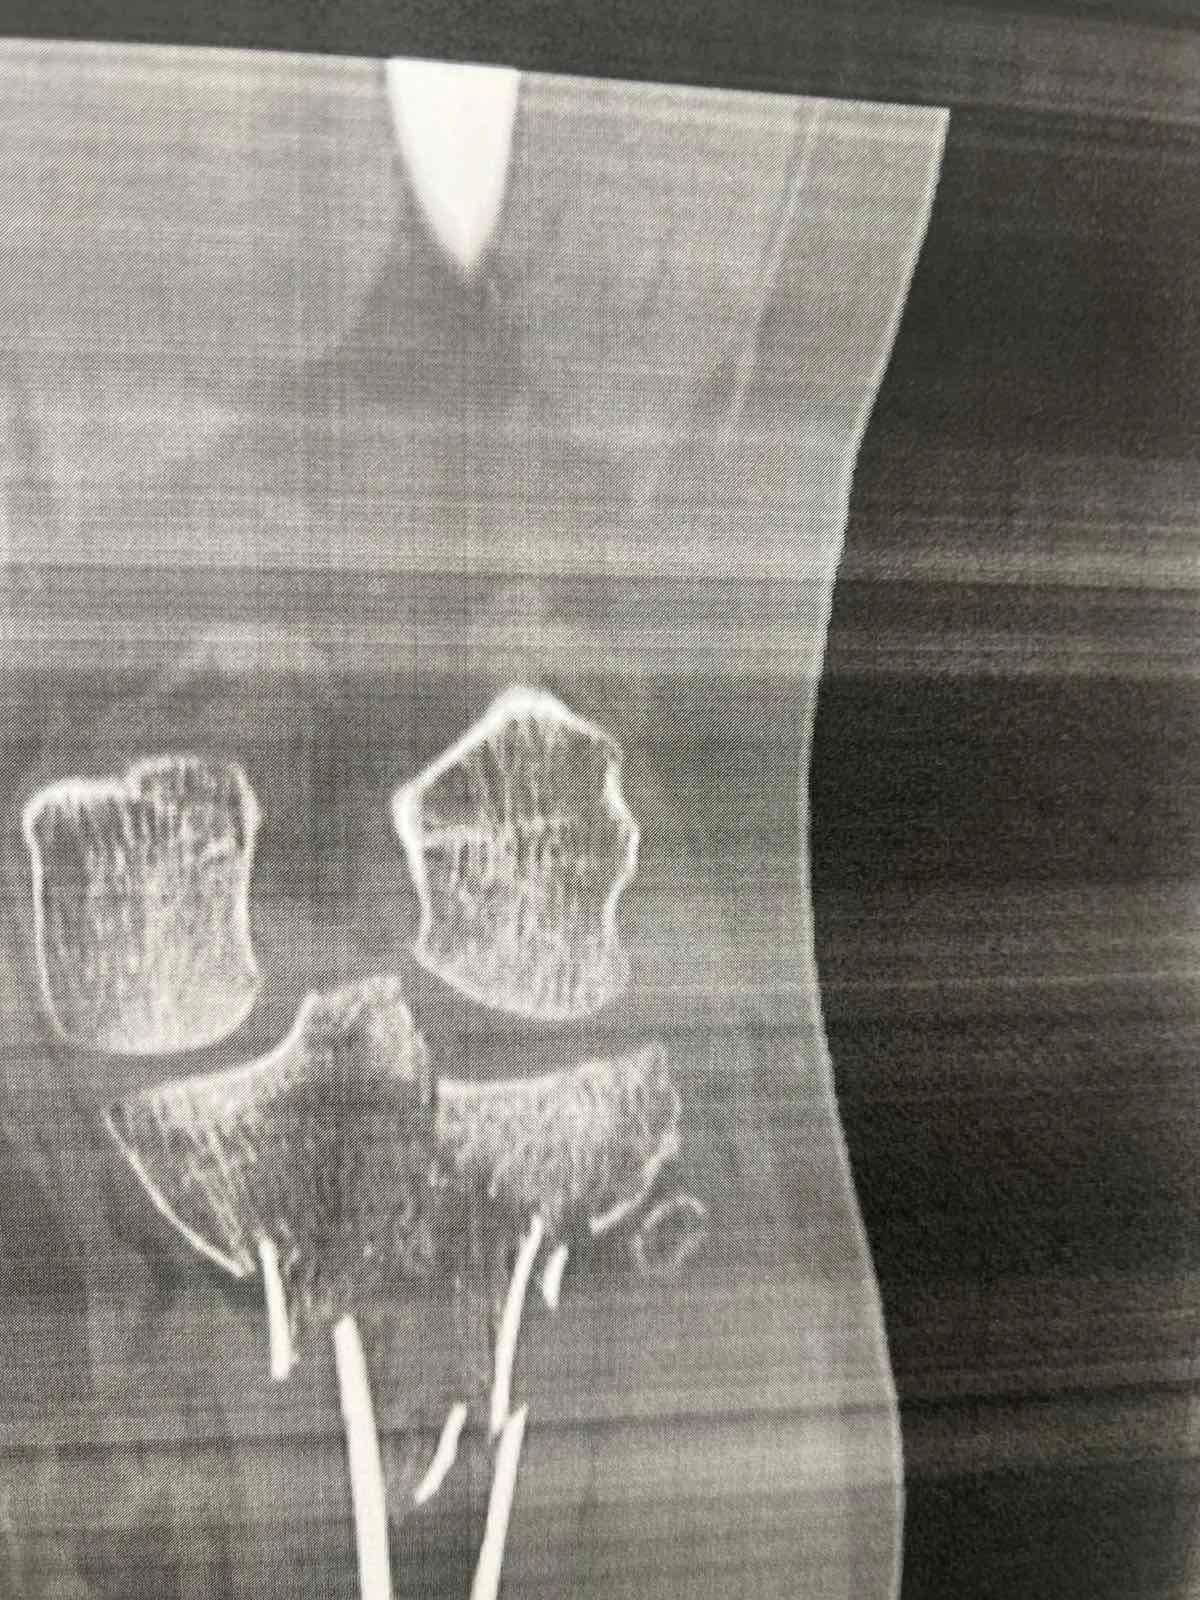

Πριν το χειρουργείο (απεικονίσεις τραυματισμού)

Τα κατάγματα του κνημιαίου πλατώ αφορούν την άνω επιφάνεια της κνήμης που συμμετέχει στην άρθρωση του γόνατος. Η ταξινόμηση Schatzker χρησιμοποιείται ευρέως για να περιγράψει το μοτίβο του κατάγματος.

Ο Schatzker τύπος VI είναι από τις πιο βαριές κακώσεις: πρόκειται για κάταγμα του πλατώ με μεταφυσιο-διαφυσιακή ασυνέχεια(δηλαδή «διαχωρισμό» της μεταφύσεως από τη διάφυση), συχνά μετά από υψηλής ενέργειας τραυματισμό. Τέτοιες κακώσεις μπορεί να συνοδεύονται από σημαντικό οίδημα/βλάβες μαλακών μορίων και απαιτούν ιδιαίτερη προσοχή στον χρόνο και στον τρόπο αποκατάστασης.